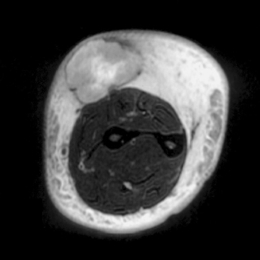

Radiographic imaging is used to help form a diagnosis. These include X-Ray, MRI, CT and Bone Scans.

An example of an MRI is shown.